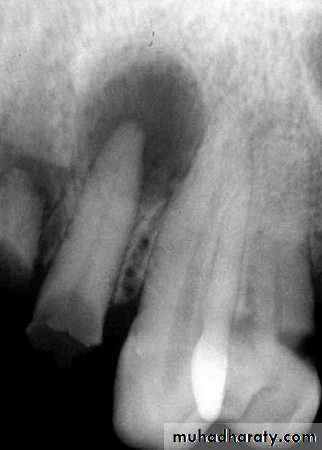

The internal appearance of a lesion can be classified into one of three basic categories: totally radiolucent, totally radiopaque, or mixed radiolucent and radiopaque (mixed density).Step 4: Analyze Effects of Lesion on Surrounding Structures Teeth

Displacement of teeth is seen more commonly with slower growing, space-occupying lesions.Lesions with an epicenter above the crown of a tooth (i.e., follicular cysts and occasionally odontomas) displace the tooth apically.